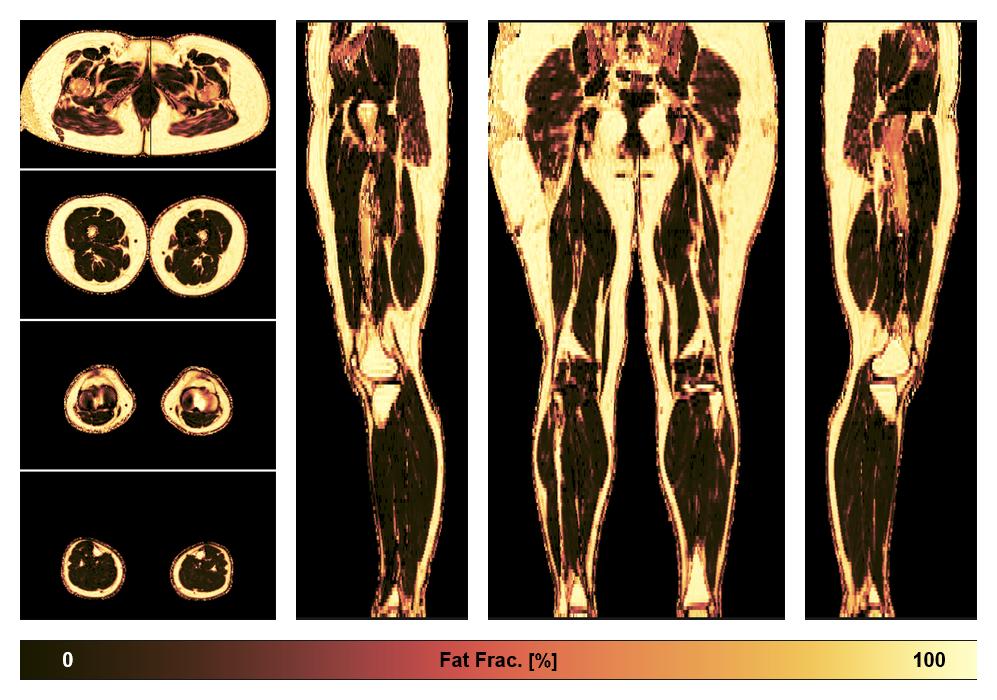

• Fat fraction

The fat fraction of the lower extremity obtained from the dixon reconstruction for muscle water fat quantification.